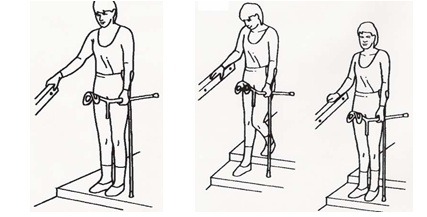

نکاتی در مورد بالا و پایین رفتن از پلهها: پلکان بدون نرده

به کمک چوبهای زیر بغلی که نزدیک به پلهها نگه داشتهاید بایستید و از پلهها بالا بروید. اول پای سالم را روی پله بالایی بگذارید، سپس پای عمل شده را بلند کنید. در انتها چوبهای زیر بغل را روی پلهها بگذارید.

برای پایین آمدن از پلهها ابتدا چوبهای زیر بغل را روی پله پایینتر بگذارید، سپس پای عمل شده و در نهایت پای سالم را روی همان پله پایینی بگذارید.

برای پایین آمدن از پلهها ابتدا چوبهای زیر بغل را روی پله پایینتر بگذارید، سپس پای عمل شده و در نهایت پای سالم را روی همان پله پایینی بگذارید.

نکاتی در مورد بالا و پایین رفتن از پلهها: پلکان با نرده

هنگام بالا رفتن از پلهها با یک دست از نردهها بگیرید و چوبهای زیر بغل را در دست دیگر بگیرید. ابتدا پای سالم را روی پله بالایی بگذارید، سپس پای عمل شده را بالا ببرید و در نهایت چوب زیر بغل را روی پله بالایی بگذارید.

هنگام بالا رفتن از پلهها با یک دست از نردهها بگیرید و چوبهای زیر بغل را در دست دیگر بگیرید. ابتدا پای سالم را روی پله بالایی بگذارید، سپس پای عمل شده را بالا ببرید و در نهایت چوب زیر بغل را روی پله بالایی بگذارید.